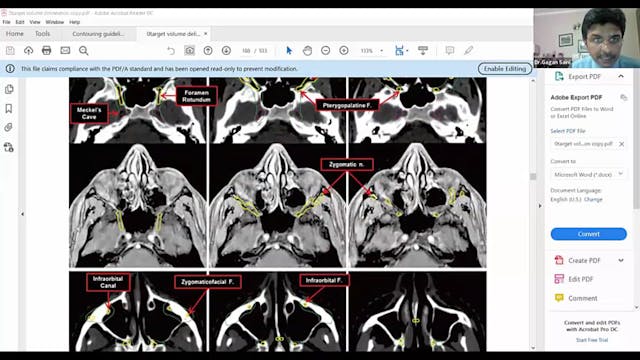

07/11/19 - Dr. Cessal Kainickal - Radiation Oncology - Head and Neck India

04/04/19 - Dr. Gagan Saini - Radiatio...

Larynx carcinoma, squamous cell carcinoma, RT volumes, role of neoadjuvant chemotherapy, carcinoma pyriform sinus, role of definitive CTRT,